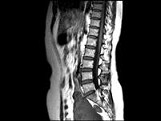

- 单项选择题女,37岁, 下腹部不适,MRI检查如图所示, 下列说法错误的是 ( )

A、子宫底部局部隆起,该病灶边界清晰

B、病灶T

WI信号与子宫肌层的信号相同C、病灶T

WI信号为明显低信号D、此为子宫粘膜下肌瘤

E、此为子宫浆膜下肌瘤